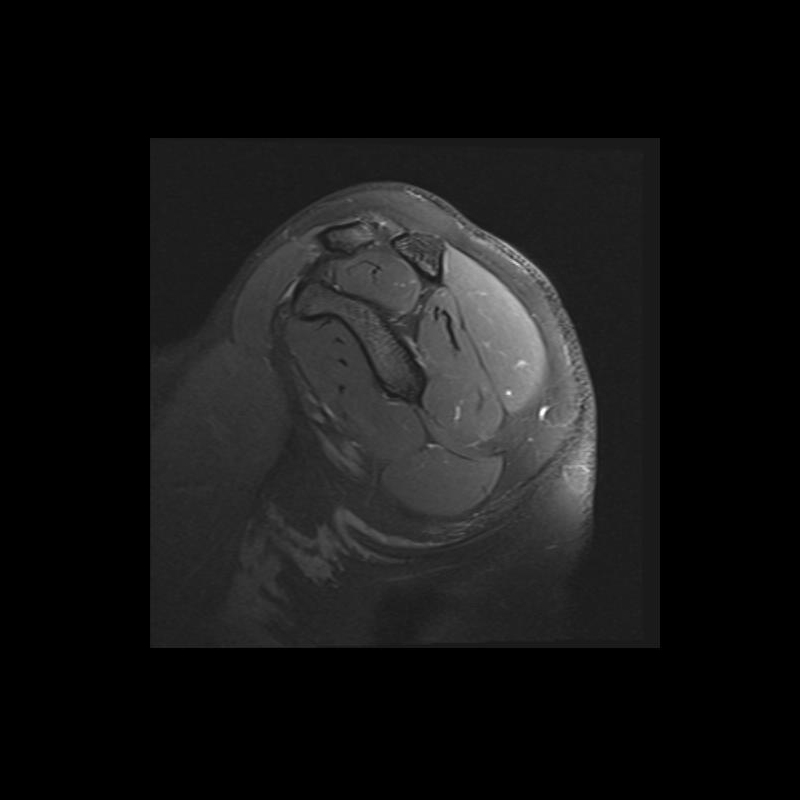

Shoulder MRI Anatomy